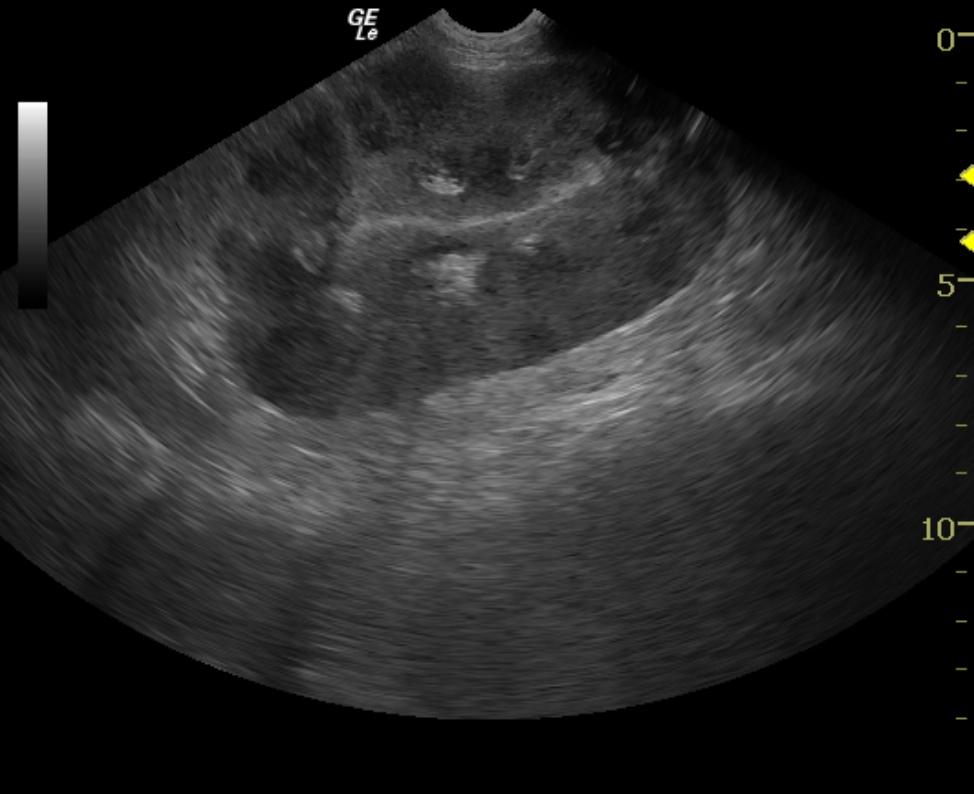

The kidneys revealed severe renomegaly (8 cm each) with multiple target type hypoechoic lesions. Round cell neoplasia is suspected. No evidence of acute or chronic inflammatory or infarctual changes were noted.

Likely bilateral renal neoplasia such as lymphoma or other round cell disease.